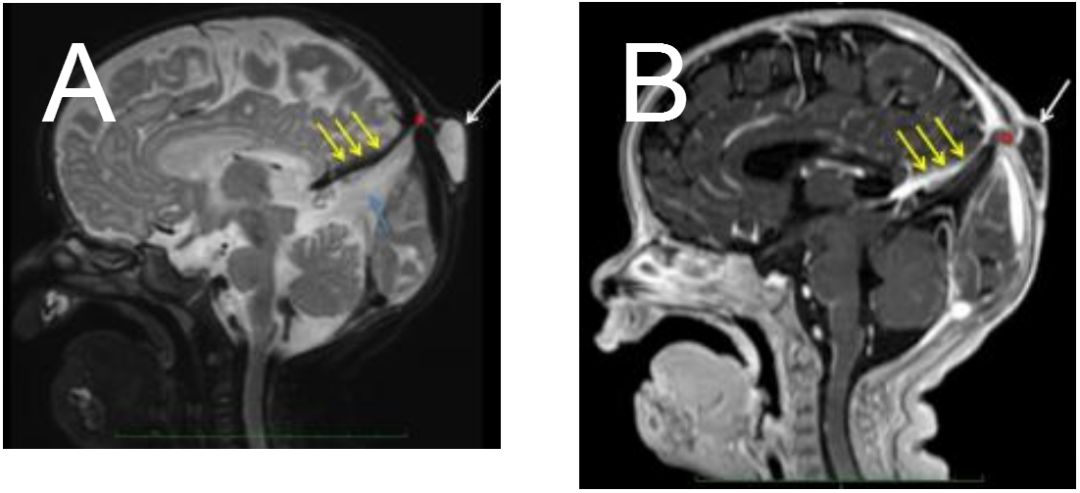

两岁女孩,有一可触及的中线顶骨软组织无痛性肿块。发育正常,神经学检查未见明显异常。影像学如下:

正中矢状面T2 (A)和3D增强T1 (B)提示一颗颅底软组织肿块(白色箭头),并通过边界清楚的骨缺损(星号)伴随脑脊液信号与颅内沟通。下矢状窦持续存在(等同于直穿静脉窦,黄色箭头)、上矢状窦局灶不连续性(星号)。小脑上池突出也可观察到小脑幕高异常嵌入(蓝色箭头)。